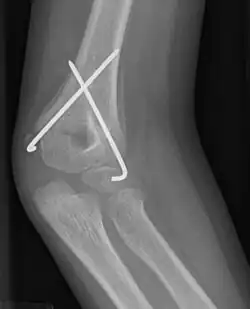

![]() Supracondylar humeral fracture, treated with closed reduction and pinning | |

Numerous pinning techniques have been proposed, however there is not enough evidence to determine which is more effective.[1] Pinning involves the manipulation, with X-ray guidance, of the fracture into an acceptable position, and the immediate insertion of metal pins, called Kirschner wires, through the skin, into one bone fragment and across the fracture line into the other bone fragment. These pins are normally left in position for some four to six weeks, and are removed when the fracture has healed.